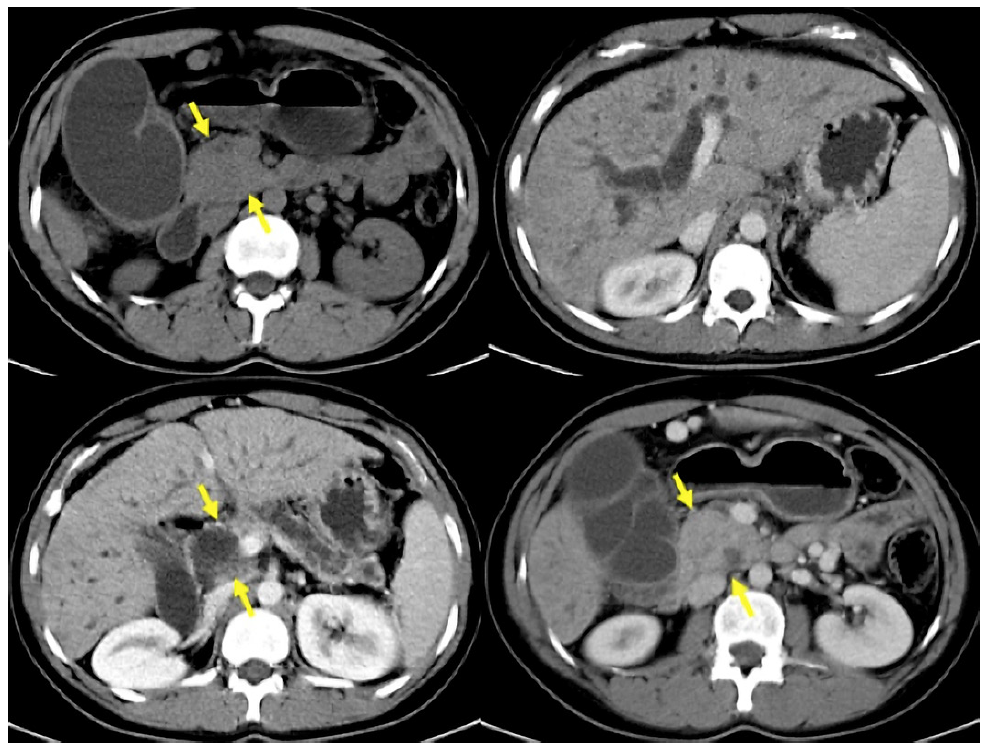

CT was performed in 44 patients. PDAC was suspected in 17 (38.67%), SPN in 10 (22.72%), pancreatic cystic lesion in 4 (9.09%), NF-NET in 4 (9.09%), chronic pancreatitis in 3 (6.81%), SCA in 2 (4.54%), pancreatic pseudocyst in 2 (4.54%), hematoma after blunt trauma in 1 (2.27%), and common bile duct dilation in 1 (2.27%) case (Fig. 2 ). The combination of CT + EUS and CT + EUS-FNA significantly increased (p < 0.005) the diagnosis compared to CT only, which went from 22.72% to 66.66% and 94.11%, respectively (Table 3). The sensitivity, specificity, positive and negative predictive value, and accuracy for the SPN diagnosis obtained by CT was 22%, 66.7%, 90%, 6%, and 25%, respectively.

Fig. 2 CT images with enlarged pancreatic head, dilatation of the main pancreatic and choledochal duct, in addition to atrophy of the pancreatic gland in a 23-year-old woman with a history of chronic alcoholism (same case in Fig. 3).